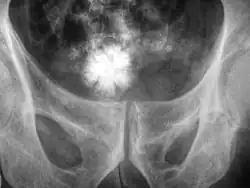

La taille des calculs varie d'un grain de sable à celle d'une balle de golf. Les plus gros, dits « coralliformes », moulent l'intérieur du rein, ayant ainsi l'aspect de branches de corail. Les calculs sont généralement évacués par miction.

Le calcium relativement dense rend ces calculs radio-opaques et ils peuvent être détectés par radiographie de l'abdomen. L'échographie, le scanner et la radiographie numérisée sont les examens de diagnostic les plus précis pour la détection des calculs.